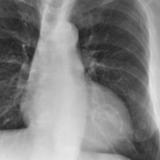

Cong Ht Disease

Album: Cong Ht Disease

Date: 03/17/2004

Size: 27 items

Views: 33818